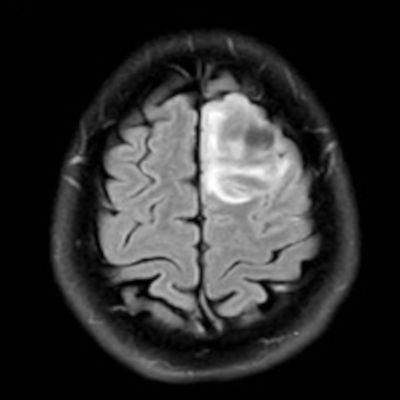

- Sol frontal kortikal-subkortikal yerleşimli aksiyel T2A görüntüde hiperintens sinyal özelliği gösteren (oklar) ve FLAIR görüntüde sinyali ağırlıklı olarak baskılanan (oklar) kitlesel lezyon izleniyor. Lezyon T1A görüntüde hipointens olup post-kontrast T1A görüntüde bu düzeyde patolojik kontrastlanma izlenmiyor (oklar).

- FLAIR’de T2’ye benzer şekilde hiperintens görünür. Ancak T2–FLAIR mismatch bulgusu, bu tümör tipi için oldukça karakteristiktir.

- T2–FLAIR mismatch bulgusu, T2AG’de homojen hiperintensite ile FLAIR görüntüde santral sinyal baskılanmasının ve çevrede hiperintens halka görünümünün bulunduğu bir fenomendir. Bu bulgu, özellikle IDH-mutant, 1p/19q kodelesyonu olmayan astrositomları tanımlamada oldukça özgül bir biomarker olarak literatürde vurgulanmıştır. Ayırıcı tanıda akla gelmesi gereken oligodendrogliomlarda T2/FLAIR mismatch bulgusu genellikle görülmez.

- Olgumuzda T2-FLAIR mismatch bulgusu mevcut olup, opere edilmiş ve tanısı histopatolojik olarak konulmuştur.